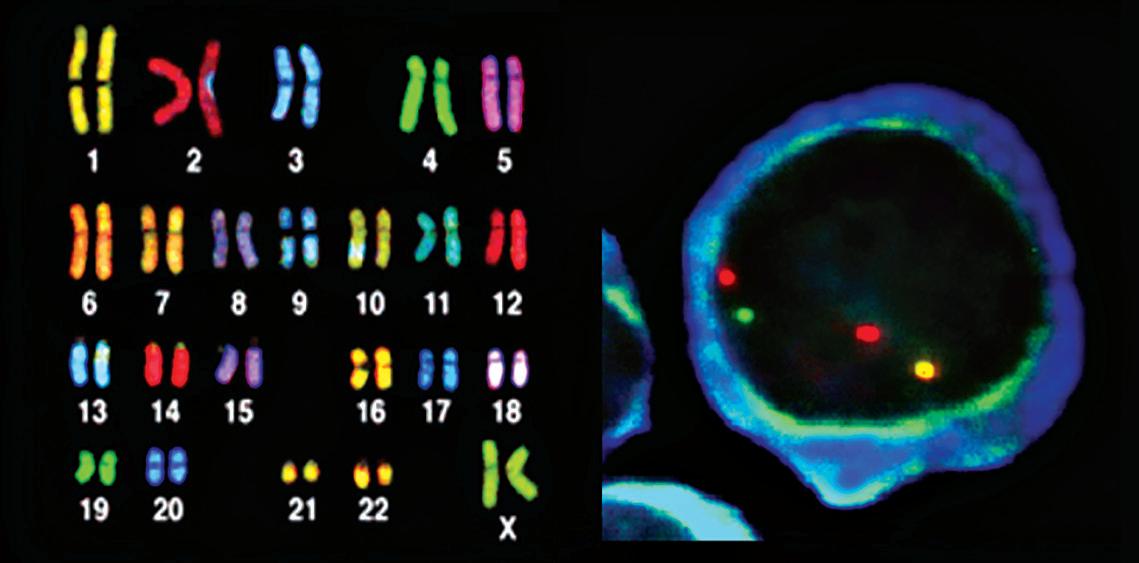

IMWG于2015年公布了修订的国际分期系统 (R-ISS),将ISS与两种染色体

异常检测相结合。我们强烈建议对诊断时采集的骨髓样本进行这两项

染色体检查:

¡ 细胞遗传学(核型分析),

¡ 荧光原位杂交 (FISH)。

图5.骨髓瘤细胞的荧光原位杂交 (FISH) 图4.人染色体核型分析 图6.高危骨髓瘤的染色体异常 缺失 易位

细胞遗传学是一种实验室检查,它对正在分裂的骨髓瘤细胞中的染色 体进行评估。骨髓瘤细胞的活跃生长率通常很低。不足 3% (通常低于 1%)的细胞正在增殖。即使存在任何染色体异常,这种评估是也不完整 的。尽管如此,一旦发现异常则有重要意义,因为这些异常出现在少数 实际生长的细胞中。

FISH 是对骨髓标本中所有骨髓瘤细胞的染色体进行分析。 FISH 检测可以 检出染色体易位、缺失片段、多余片段及染色体丢失。无论骨髓瘤细 胞是否正在生长, FISH 都能检出异常。在骨髓样本中加入发出荧光(发 光)的特殊基因探针。这些探针追踪细胞分裂后的遗传物质,并发出信 号表明是否存在已知骨髓瘤中会发生的染色体异常。

不同的染色体标注不同颜色的探针。例如,如果 4 号染色体的遗传物质 错误地与 14 号染色体连接,那么标注这些染色体遗传物质的不同颜色 的点将出现在一起,提示高危异常 t(4;14) ,它代表“ 4 号和 14 号染色体 之间的遗传物质易位”。其他被视为高危的异常有 t(14;16) 和 t(14;20) 、